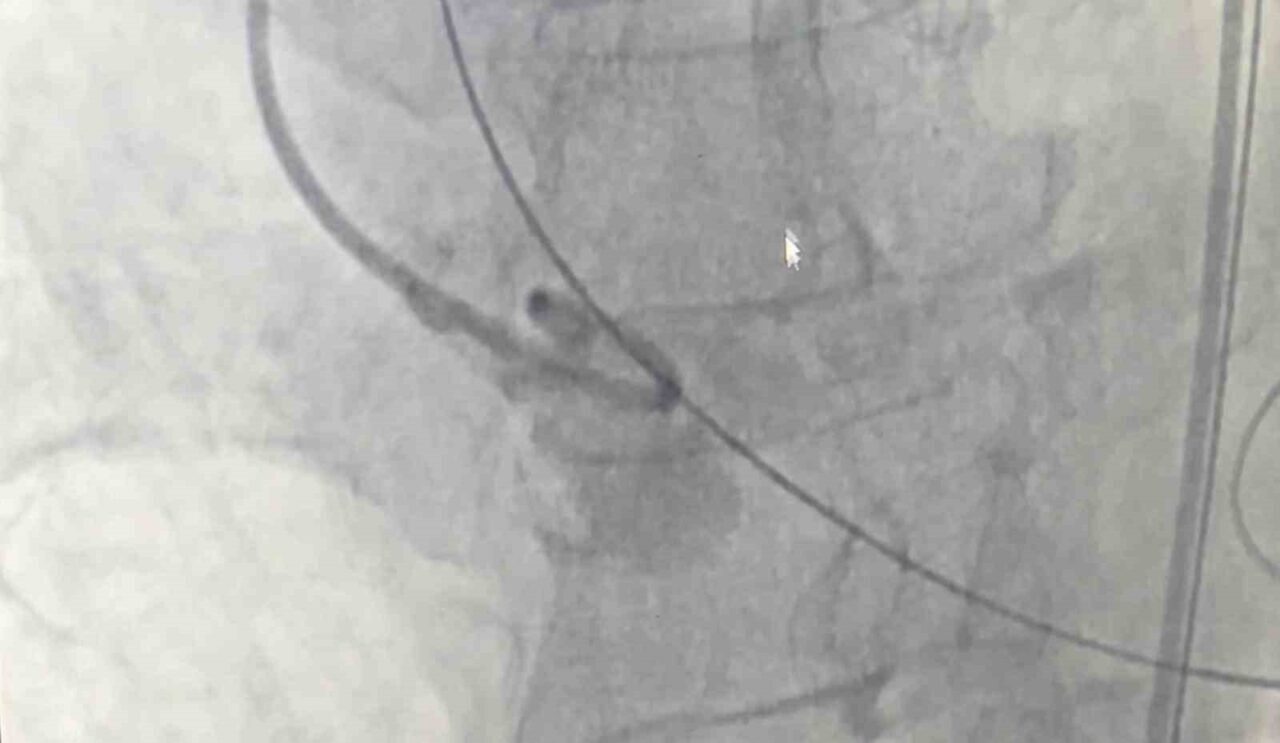

Samsun Eğitim ve Araştırma Hastanesi’nde 80 yaşındaki bir hastaya, nadir görülen dört yaprakçıklı aort kapağı nedeniyle transkateter aort kapak implantasyonu (TAVİ) yöntemiyle başarılı bir operasyon gerçekleştirildi. Operasyon, bu özelliği taşıyan vakalar arasında dünyada 18’inci, Türkiye’de ise ilk olma özelliği taşıyor.

Amasya’nın Merzifon ilçesinde yaşayan Muzaffer Uslu (80), göğüs sıkışması ve baygınlık şikayetleriyle başvurduğu Merzifon Devlet Hastanesi’nden Samsun Eğitim ve Araştırma Hastanesi’ne sevk edildi. Tetkikler sonucu, normalde üç yaprakçıklı olması gereken aort kapağının dört yaprakçıklı olduğu belirlendi. Samsun Üniversitesi Tıp Fakültesi Kardiyoloji Ana Bilim Dalı Öğretim Üyesi Doç. Dr. Mustafa Yenerçağ, kapak değişiminin açık ameliyatla yüksek risk taşıması nedeniyle kapalı yöntem olan TAVİ işlemiyle çözüm sağladıklarını söyledi.

Doç. Dr. Yenerçağ, işlem öncesi yapılan tetkiklerde karşılaştıkları nadir bulgu hakkında ise “Hastanın TAVİ işleminden önce yapılan tetkiklerinde aort kapağının 3 yaprakçıklı olması beklenirken çok daha nadir görülen ‘Quadricuspid’ adı verilen 4 yaprakçıklı aort kapağı saptadık. Daha önce böyle bir vaka ile karşılaşmamıştık. Literatürleri, akademik çalışmaları inceledik. 4 yaprakçıklı aort kapağının toplumda 100 bin kişide 4 görüldüğünü, taradığımız uluslararası yayınlarda ise 4 yaprakçıklı aort kapağı bulunan sadece 17 hastaya TAVİ işlemi yapıldığını saptadık. Ülkemizden bildirilen vaka örneği bulamadık. Diğer ülkelerde yapılan vakaları detaylıca inceledik. İleri tomografik analizleri yaptık. Vakamıza detaylıca hazırlandık” dedi.

“Doç. Dr. Serkan Sivri, asistan doktorlarımız Berkan Öztürk ve Enes Kaya ile Anestezi Uzmanı Aynur Kaynar hocamızla beraber ekip halinde hastamıza başarılı TAVİ işlemini yaklaşık 50 dakika içerisinde tamamladık. Hastamızı 1 gün yoğun bakımda takip ettikten sonra servis takibine aldık. Nadir görülen bu 4 yaprakçıklı aort kapağına yaptığımız TAVİ işleminin prosedürel detaylarını literatüre kazandırmayı planlıyoruz. Bizden sonra bu nadir vaka ile karşılaşan meslektaşlarımıza yol göstermesi açısından referans olacaktır.”